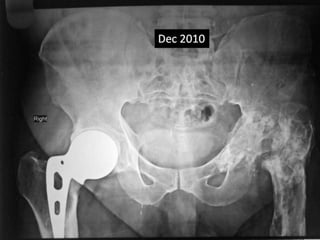

Case summary •Last follow up Nov 2014. • Showing metal fatigue with broken stem of AMP. • Patient has no pain in thigh. • A crack is seen in April 2012 as a incidental finding on x-rays. • AMP stood the test of time.

• Last follow up Nov 2014.

• Showing metal fatigue with broken stem of

AMP.

• A crack is seen in April 2012 as a incidental

finding on x-rays.

• AMP stood the test of time.